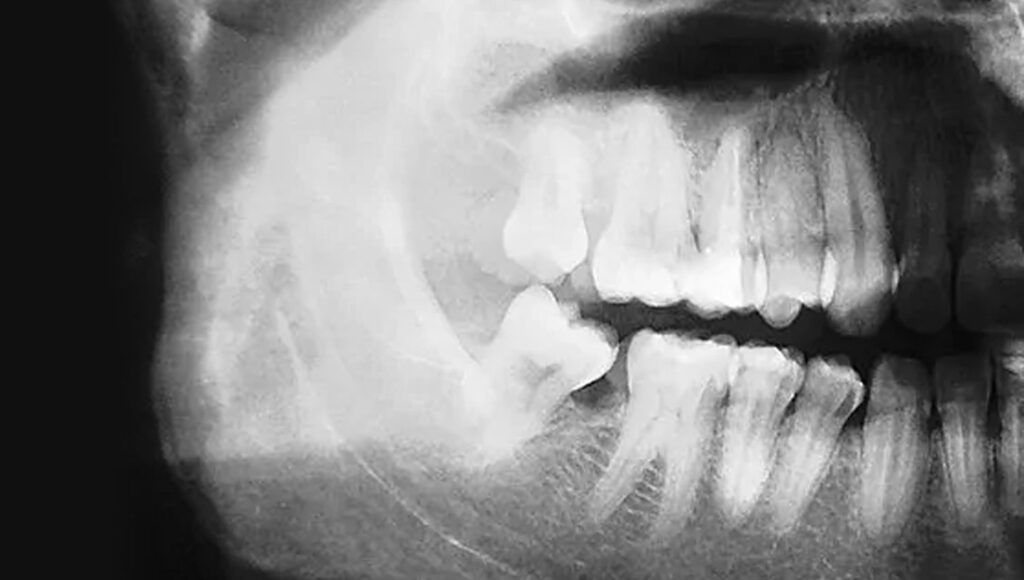

AI Detects Osteoporosis With High Accuracy By Analyzing Dental XRays Dental Treatment Of Osteoporosis a 2011 ada csa report developed by an expert panel provides potential treatment management. most osteoporosis medicines work by reducing the rate at which your bones break down. dental implants are generally considered a safe and effective tooth replacement option if you have osteoporosis. While osteonecrosis of the jaw can occur spontaneously, it more. how do. Dental Treatment Of Osteoporosis.